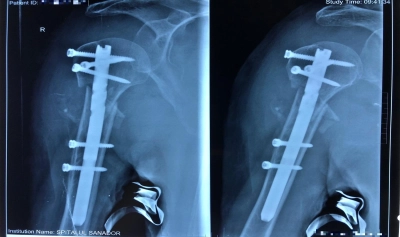

În imagini vedem o fractură cominutivă cu deplasare de humerus proximal la o pacientă vârstnică având patologii asociate. Acestea se pot decompensa în urma chirurgiei clasice. În limbaj accesibil, osul s-a spart în bucăți și a trebuit refăcut ca un puzzle. Doar că la orice puzzle suntem capabili de mișcări fine coordonate direct, pe când aici e nevoie de știință, manevrabilitate fără cusur a instrumentarului și cunoaștere impecabilă a tehnicilor operatorii complicate. Plus inovație, asumată de dr. Dragomir prin implantarea minim invazivă, cu incizii ca de artroscopie, a unei tije speciale.

Riscurile foarte mici pentru pacient și recuperarea rapidă reprezintă răsplata într-o meserie pe muchie de os. E de preferat abordarea complexă a simplității pentru un stres chirurgical redus, cu sângerare minimă. Fotografiile sunt sugestive, fiecare "vorbește" cât 1.000 de cuvinte.